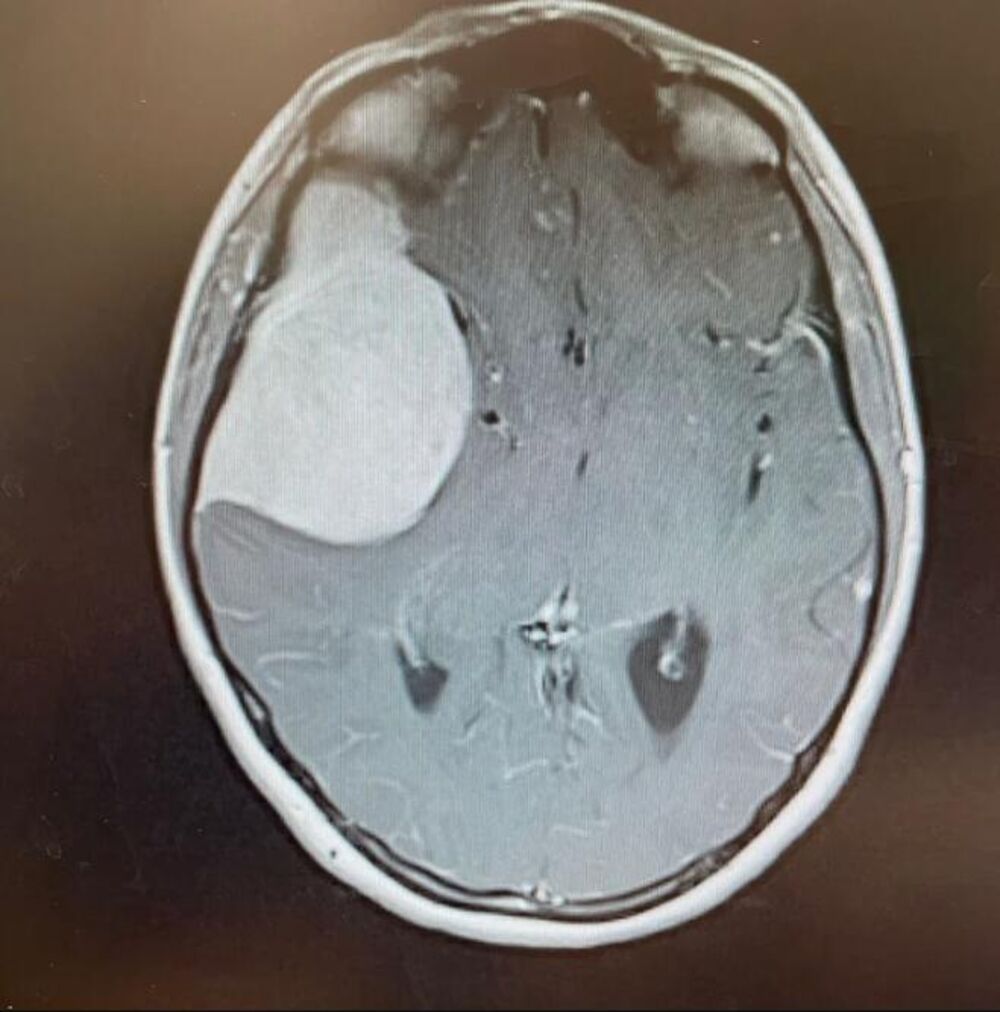

Holi Vorsvik 2021. godine otišla je na očni pregled. Međutim, ubrzo se pretvorio u hitnu situaciju kada je oftamolog primetio nešto neobično i odmah je uputio u bolnicu. Tamo su magnetna rezonanca i CT otkrili ozbiljnu dijagnozu – veliki tumor na mozgu.

Lekari su reagovali munjevito, pa je operisana u roku od 48 sati. "Da nisam otišla na taj pregled, verovatno danas ne bih bila ovde, jer je tumor bio veličine grejpa", rekla je Holi, naglašavajući koliko joj je pravovremena reakcija stručnjaka spasila život.

U bolnici u Salfordu lekari su nakon daljih analiza zaključili da su potrebni dodatni zahvati. Već narednog dana operisana je kako bi se uklonio tumor i uzela biopsija. Srećom, ispostavilo se da je tumor bio dobroćudan.